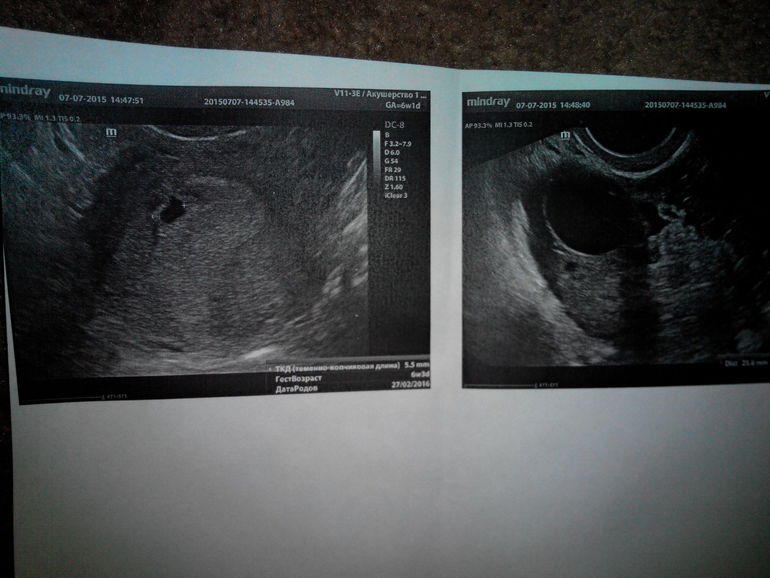

Узи - динамика

29,06

это сегодня.

что скажете?

07.07.2015

не может быть беременности без жёлтого тела. Что-то не то на УЗИ. Видимо,это не фолликулярная киста,а киста жёлтого тела.

Узистка тупая,в прямом смысле. Говорит, эмбрион вроде и есть,но лучше напишем не визуализируется.. Потом по размерам,мерят 22,ой 25.. Ну и мелочи..На первом узи есть про желтое тело, значит это оно и есть ,а не киста..